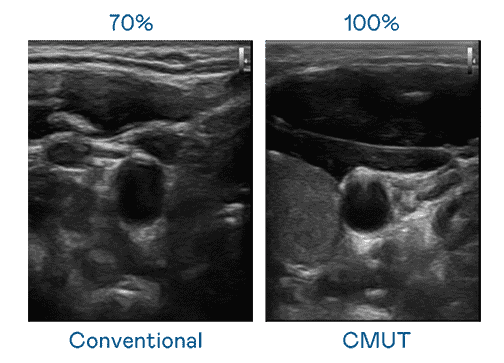

CMUT 技术是一种用电容式微机电元件来产生超音波讯号的技术。。。与传统 PZT 压电式技术相比,,,,CMUT 频宽增加 30%,,,,更宽频的超音波讯号让影像解析度大幅提升,,是实现高影像品质医疗超音波扫描、、、促进精准医疗发展的关键技术。。

大频宽带来超清晰影像

超音波影像的解析度高低,,,,首先取决于探头能发出的讯号频宽。。。尊龙集团 CMUT 可提供高清晰的超音波讯号,,,,提供高频宽、、高灵敏度、、影像纹理细节更高的超音波影像,,,协助医护人员缩短影像判读时间及利用精准的医疗影像进行诊断。。。